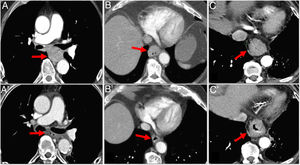

Assessment of response with multidetector computed tomography after neoadjuvant therapy in 3 different cases of oesophageal cancer (OC). A) Middle thoracic OC (arrow) with complete radiological response after neoadjuvant therapy (arrow in A'). B) OC (arrow) showing partial shrinkage after neoadjuvant therapy consistent with partial response (arrow in B'). C) Lower thoracic OC (arrow) showing no significant changes after neoadjuvant therapy (C arrow) consistent with stable disease.